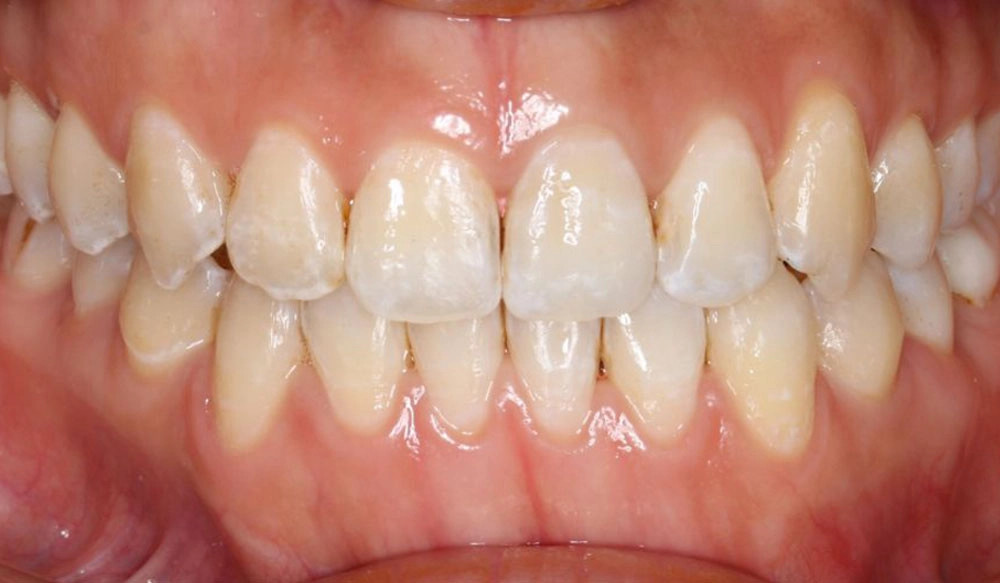

Narrow Arches

Narrow arches is the condition in which the transverse width of the maxillary and/or mandibular arches is too narrow for the teeth to properly align and have good occlusal contact.

Patient Information:

Age: 21

Gender: Female

Invisalign Treatment Option: Invisalign Comprehensive

Total Treatment Time:

11 months